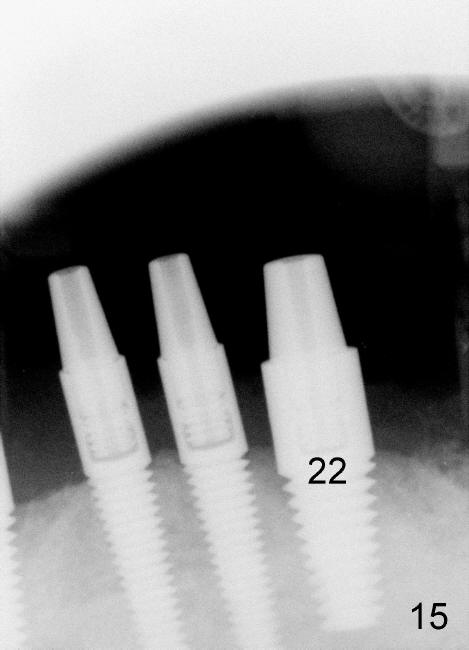

The 4 anterior implants appear to have been osteointegrated 5 months postop (Fig.14,15). More gingiva has covered the top portion of the implants (Fig.16). Ball abutments are placed for an overdenture (Fig.17).